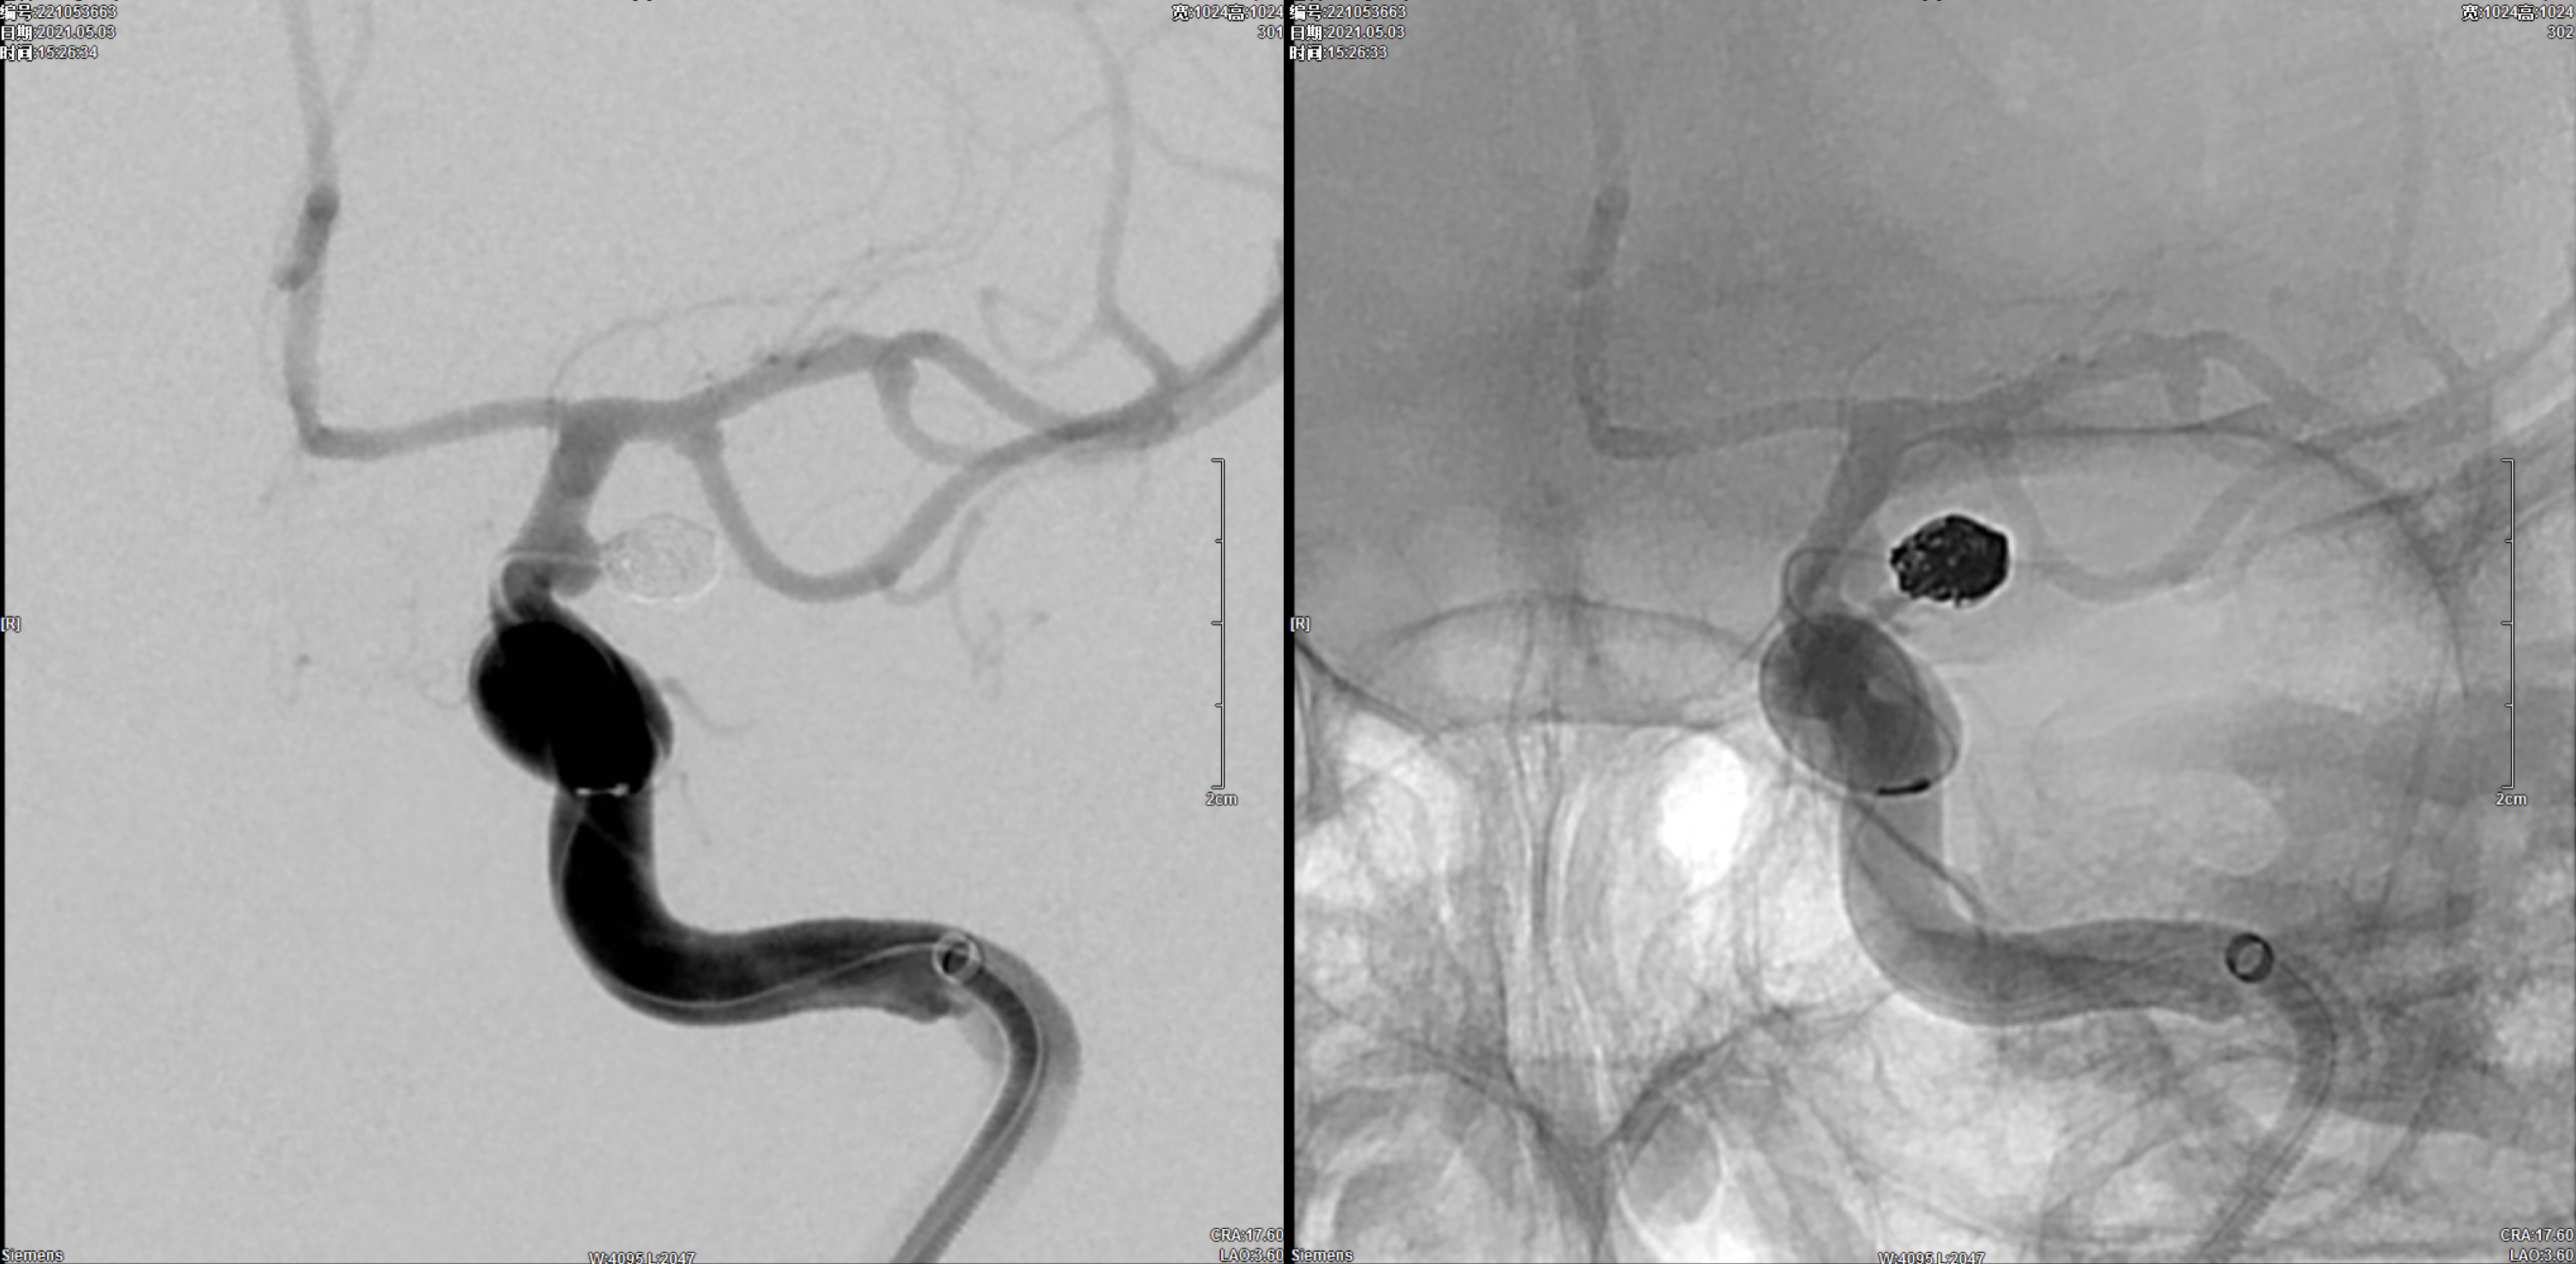

右侧颈内动脉正侧位造影:颈内动脉多发动脉瘤(眼动脉段及后交通段)。

右侧颈内动脉三维重建:颈内动脉多发动脉瘤(眼动脉段及后交通段)

左侧颈内动脉正侧位造影:颈内动脉后交通动脉瘤。